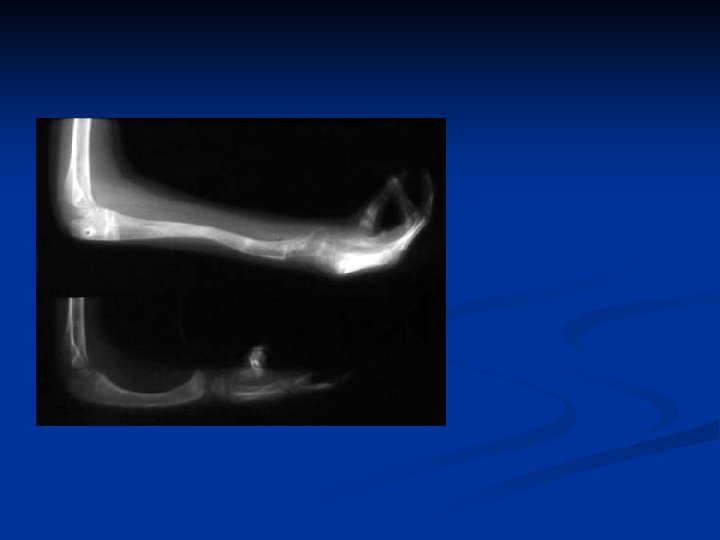

Distal Ulnar Osteotomy Reorient Original Ulno Carpal Psuedo Joint

16 y Radial clubhand 1 y centralization 2 y pollicization

12 Feb 03 Osteotomy R ulna + application TSF Intraop Post-op

During distraction

4 months post op.